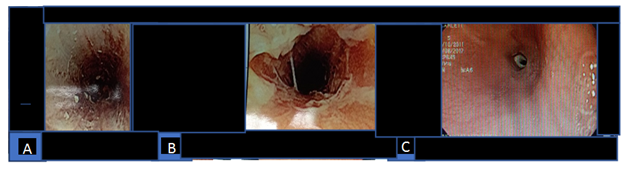

Figure 2 A and B,esophagic caustic burns one day after liquid caustic ingestion. C, tiny lumen stricture al 19cm from incisors, 51days after caustic ingestion.